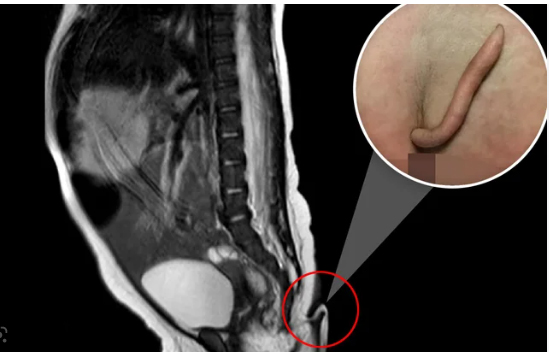

ମେକ୍ସିକୋ ସିଟି: ମେକ୍ସିକୋ ସିଟିରେ ମେଡିକାଲ ସାଇନ୍ସର ଏକ ଦୁର୍ଲଭ ଘଟଣା ସମ୍ମୁଖକୁ ଆସିଛି । ଏଠାରେ ଏକ ଶିଶୁ କନ୍ୟା ଜନ୍ମ ହେବା ପରେ ସମସ୍ତେ ଆଶ୍ଚର୍ଯ୍ୟଚକିତ ହୋଇ ଯାଇଥିଲେ । ଏହି ସୁସ୍ଥ ଶିଶୁ କନ୍ୟାର ୫.୭ ସେଂଟିମିଟର ଲମ୍ବର ଏକ ଲାଙ୍ଗୁଡ ଥିଲା । ଏହାର ବ୍ୟାସ ୩ରୁ ୫ ମିିଲିମିଟର ରହିଥିଲା । କିଛି ଦିନ ମଧ୍ୟରେ ଏହା ୦.୮ ସେଂଟିମିଟର ବଢ଼ି ଯାଇଥିଲା । ତେବେ ଡାକ୍ତରଙ୍କ ପରାମର୍ଶକ୍ରମେ ଏହି ଲାଙ୍ଗୁଡକୁ ଅପରେଶନ କରି ବାହାର କରି ଦିଆ ଯାଇଥିଲା । ନ୍ୟୁବୋ ଲିୟୋନରେ ଜଣେ ବିବାହିତ ମହିଳାଙ୍କ ସିଜେରିଆନ ମାଧ୍ୟମରେ ଏହି କନ୍ୟା ଜନ୍ମ ହୋଇଥିଲା । ଏହି ଲାଙ୍ଗୁଡରେ କୌଣସି ଯନ୍ତ୍ରଣା କିମ୍ବା କିଛି ଅସୁବିଧା ପରିଲକ୍ଷିତ ହେଉ ନ ଥିଲା ।

ଶେଷରେ ଲିମ୍ବର୍ଗ ପ୍ଲାଷ୍ଟି କରାଯାଇ ଏହାକୁ ହଟା ଯାଇଥିଲା । ବିଶ୍ୱରେ ଏ ପର୍ଯ୍ୟନ୍ତ ଏ ଭଳି ୪୦ଟି କେସ ସମ୍ମୁଖକୁ ଆସିଛି । ଡାକ୍ତରମାନେ ଏହି ଲାଙ୍ଗୁଡକୁ ୨ ଭାଗରେ ଭାଗ କରାଯାଇଛି । ପ୍ରଥମକୁ ୱେଷ୍ଟଜିୟଲ ଟେଲ ଏବଂ ଦ୍ୱିତୀୟକୁ ଟ୍ରୁ ଟେଲ ଶ୍ରେଣୀରେ ରଖାଯାଇଛି । ଟ୍ରୁ ଟେଲରେ ହାଡ ନ ଥାଏ । ଏଥିରେ କେବଳ ଟିଶୁ ଓ ଫ୍ୟାଟ ରହିଥାଏ । ୨୦୨୧ରେ ବ୍ରାଜିଲରେ ଏ ଭଳି ଏକ ଶିଶୁ ଜନ୍ମ ହୋଇଥିଲା ।